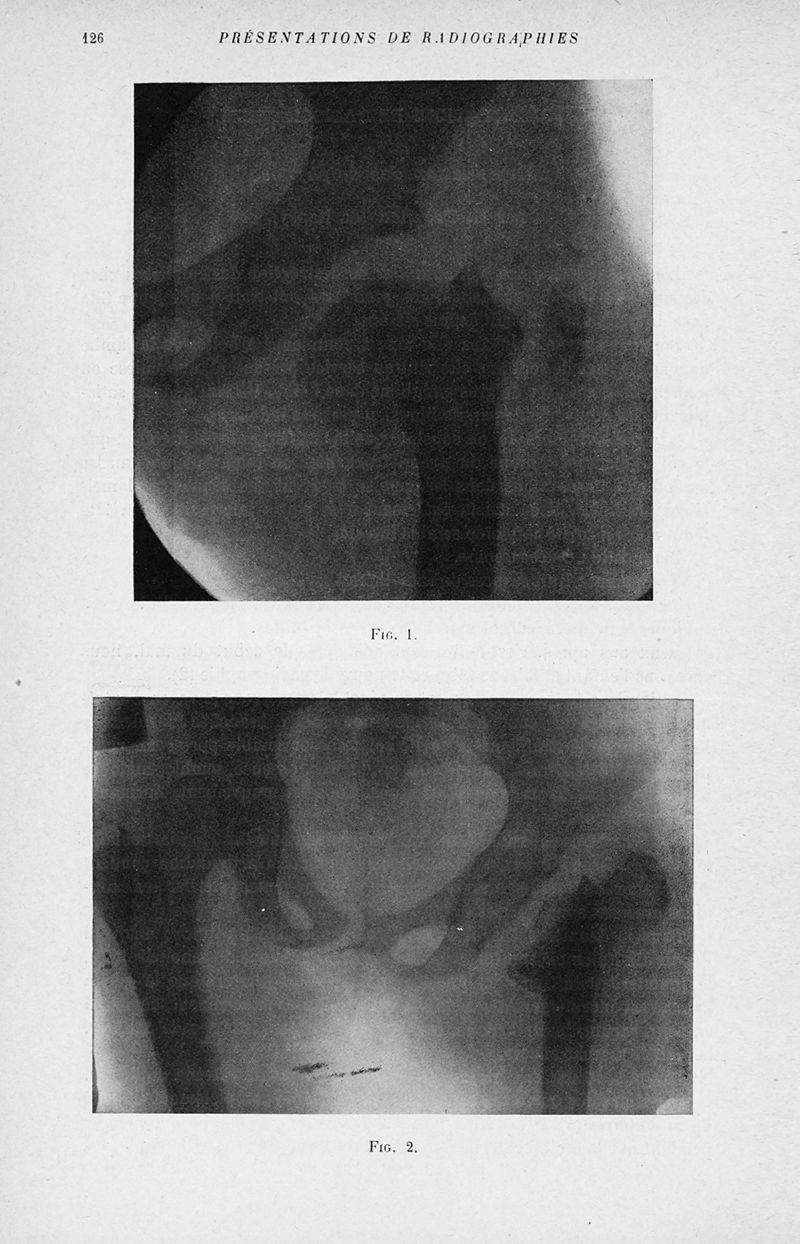

Bulletins et mémoires de la société nationale de chirurgie

Tome LI, 1925. - Paris : Masson, 1925.